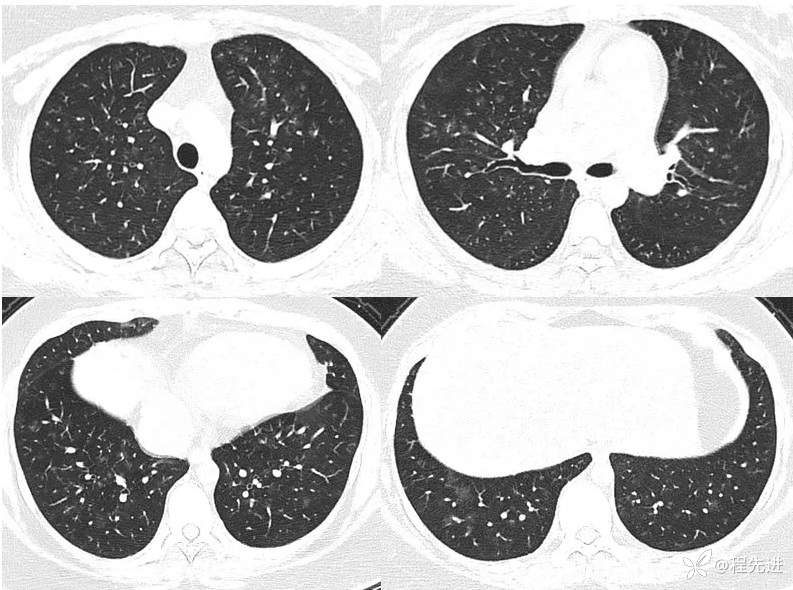

一月余前CT: